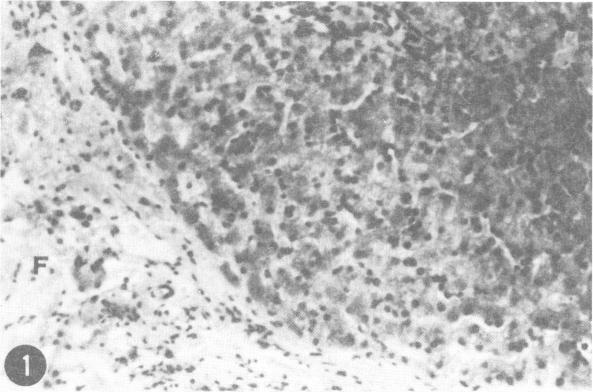

Inherited copper toxicity of the liver in Bedlington terriers.

摘要